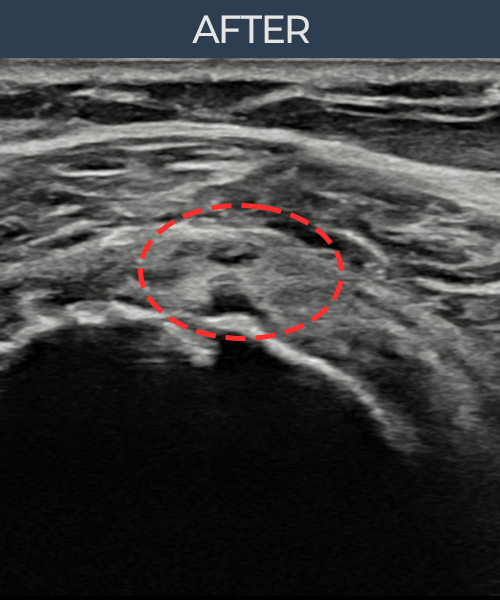

김ㅇㅇ님 · 좌측 극상근건 부착부 광범위 부분파열

좌측 어깨 극상근건 광범위 파열로 수개월간 일상생활이 어렵던 중 내원하셨습니다. 초음파 검사에서 부착부 광범위 부분파열이 확인되었으며, 어깨인대 축소봉합술 시행 후 힘줄 구조가 회복되었습니다.